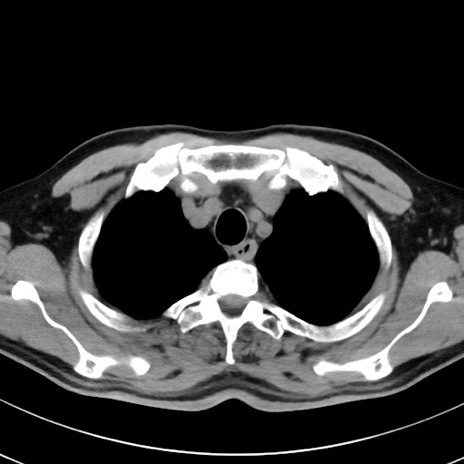

【腹部TIPS】症例29 参考症例 CT(横断像)

症例

70歳代男性